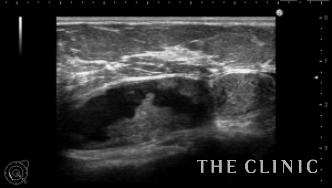

本日はシリコンバッグを抜去した後に注入脂肪がカプセル内に流入してしこりになった症例を紹介します。

カプセル内のしこりはカプセル内をしこりが移動するので治療が難しいです。

乳腺下の5㎝のしこりです。

このしこりがカプセル内を移動するので、エコーのプローブで移動しないように圧迫固定して穿刺吸引しました。